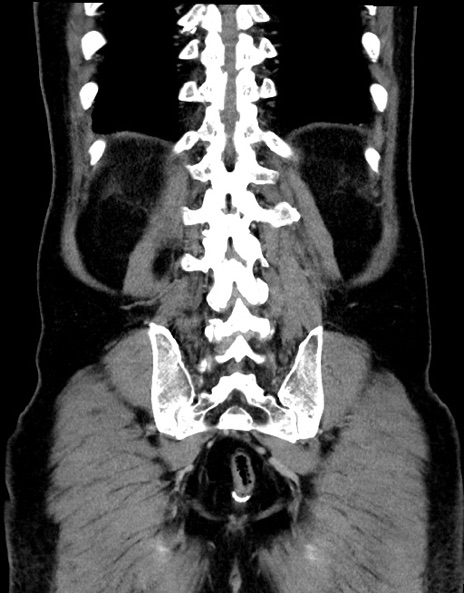

症例15(冠状断像)

【症例】70歳代男性

【主訴】腹痛

【現病歴】今朝から腹痛あり。全体的に痛い。特に左上の方。排ガスが今日はない。冷や汗が出る。

【既往歴】直腸癌術後

【身体所見】左側腹部〜上腹部に圧痛あり。腹膜刺激症状明らかなではない。軽度反跳痛。左下腹部に術後瘢痕あり。

【データ】WBC 7700、CRP 0.02